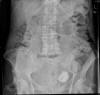

Diverticulosis de colon.

Diverticulosis de colon. Megacolon.

Sistema ureterocalicial doble

Dilatación colónica. Diverticulosis.